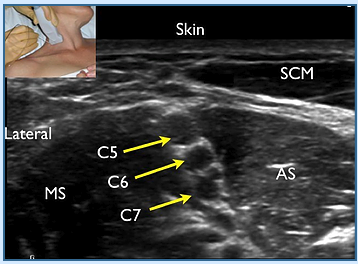

Identify the Block and Following Structures

Complications?

What is a “3 in 1” Block

What Nerves Are Blocked?